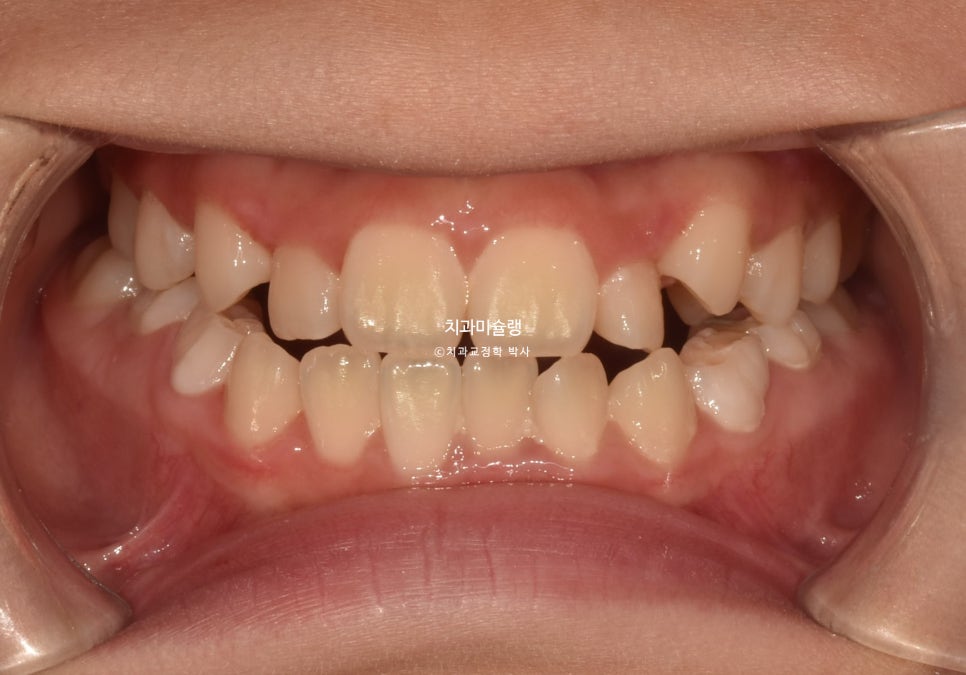

초진 시 상태 및 진단

24년 6월, 교정치료를 위해 내원한 만 10세 어린이 입니다.

송곳니 덧니와 개방교합이 보입니다.

고치고 싶은것은 ‘덧니’ 입니다.

위 앞니가 아래 앞니를 덮지 못하고 아래 앞니가 더 앞으로 나가있는 반대교합 입니다.

안모에서는 아래턱이 발달한 주걱턱 양상이 보입니다.

주걱턱의 의학적 정식 명칭은 골격성 3급 부정교합 이라고 합니다.